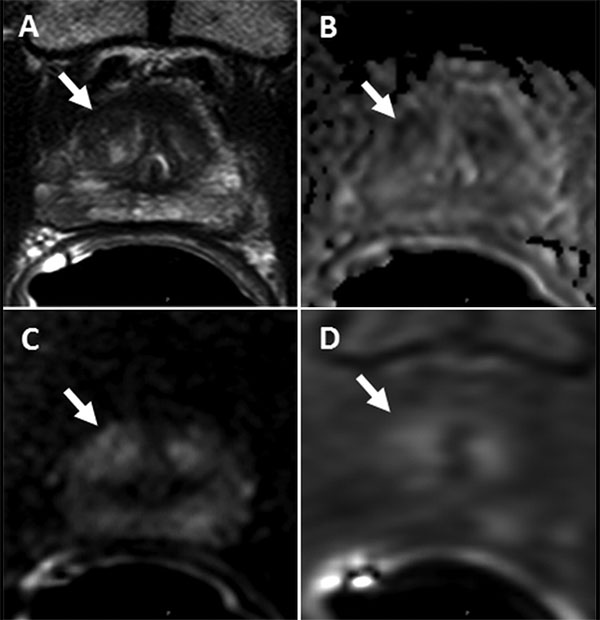

Images of a lesion (arrow) in a 73-year-old man with a serum prostate-specific antigen level level of 4.08 ng/mL. A, Axial T2-weighted MR image shows the 1.1-cm lesion in the left apical anterior transition zone. B, Apparent diffusion coefficient map shows marked diffusion restriction in this same lesion. C, Diffusion-weighted (DW) MR image (b = 2000 sec/mm2). D, Dynamic contrast-enhanced (DCE) MR image shows early enhancement. The lesion was assigned a Prostate Imaging and Reporting Data System (PI-RADS) score of 4 with T2-weighted and DW MR imaging and had an overall PI-RADS score of 4. Fusion MR imaging and transrectal US–guided biopsy revealed Gleason 3+3 prostate cancer within this lesion.Choyke et al. Radiology 2018; © RSNA 2018.